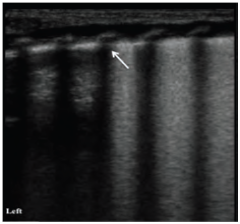

In a typical lung the pleura shows up as a normal echogenic line moving persistently amid breath.5 ‘A lines’, are equidistant lines parallel to straight solid pleural lines, and are reverberation artefacts (Figure 1). B-lines occur when sound waves pass through the pleural line encountering a mixture of air and water as in pulmonary oedema (Figure 2). These are discrete laser-like vertical hyper echoic lines that arise from the pleural line, extend to the bottom of the screen without fading, and move synchronously with lung sliding. The pleural line slides from side to side with respiration and represents movement of the pleural surface with the respiratory cycle. This sign is known as sliding sign, a normal lung feature.6-8 Due to the presence of fluid in normal neonatal lung, B-lines can be found in first few days in normal neonates too.9 In TTN, there are very compact B lines in the inferior pulmonary fields and not so compact B lines in the superior lung field giving a characteristic double lung point sign. Coexistence of lung consolidation, abnormal pleural line (thickness of >0.5mm or blurred), bilateral white lung and disappearance of A lines are constant ultrasonography features of RDS with a specificity and sensitivity of 100%. The most important indicator of RDS is consolidation and the extent and scope of consolidation varies with severity of RDS. Consolidation in moderate RDS is sub pleural and focal in nature whereas consolidation in severe RDS is more widespread and deep.10,11 (Figure 3, 4).

Figure 1 Normal lung ultrasound showing Horizontal A lines equidistance from each other.